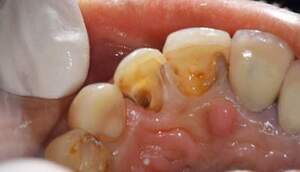

左の写真は歯が歯肉縁上にないのがわかります。右では歯肉縁上に1周にわたって歯牙があるのがわかります。

レントゲンで見ても、右上2では歯質が歯肉縁上にのこっていない。しかし歯根は長いのでMTMの適応症例です。